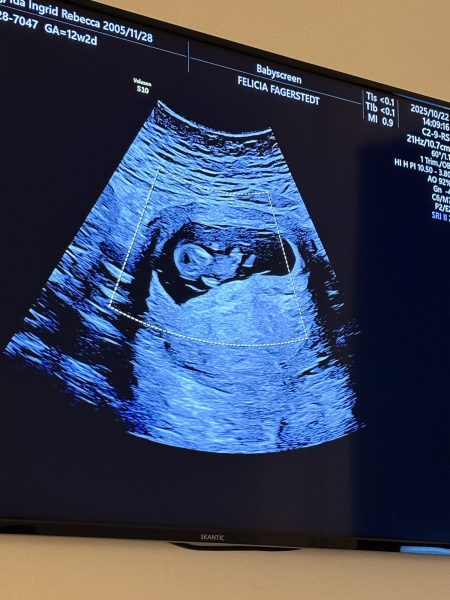

Idag gjorde Ida ett ultraljud. Lilla bebisen har allt ❤️ ett hjärta som slår, armar och ben och massor av energi. Eftersom inte barnets pappa vill ta del av sitt barn och uppleva allt det fantastiska kring graviditeten så ställer Idas bästa vän Diona upp med kärlek, glädje och inspiration ❤️

Beräknad förlossning är 19 maj nästa år ❤️ ser fram emot det!